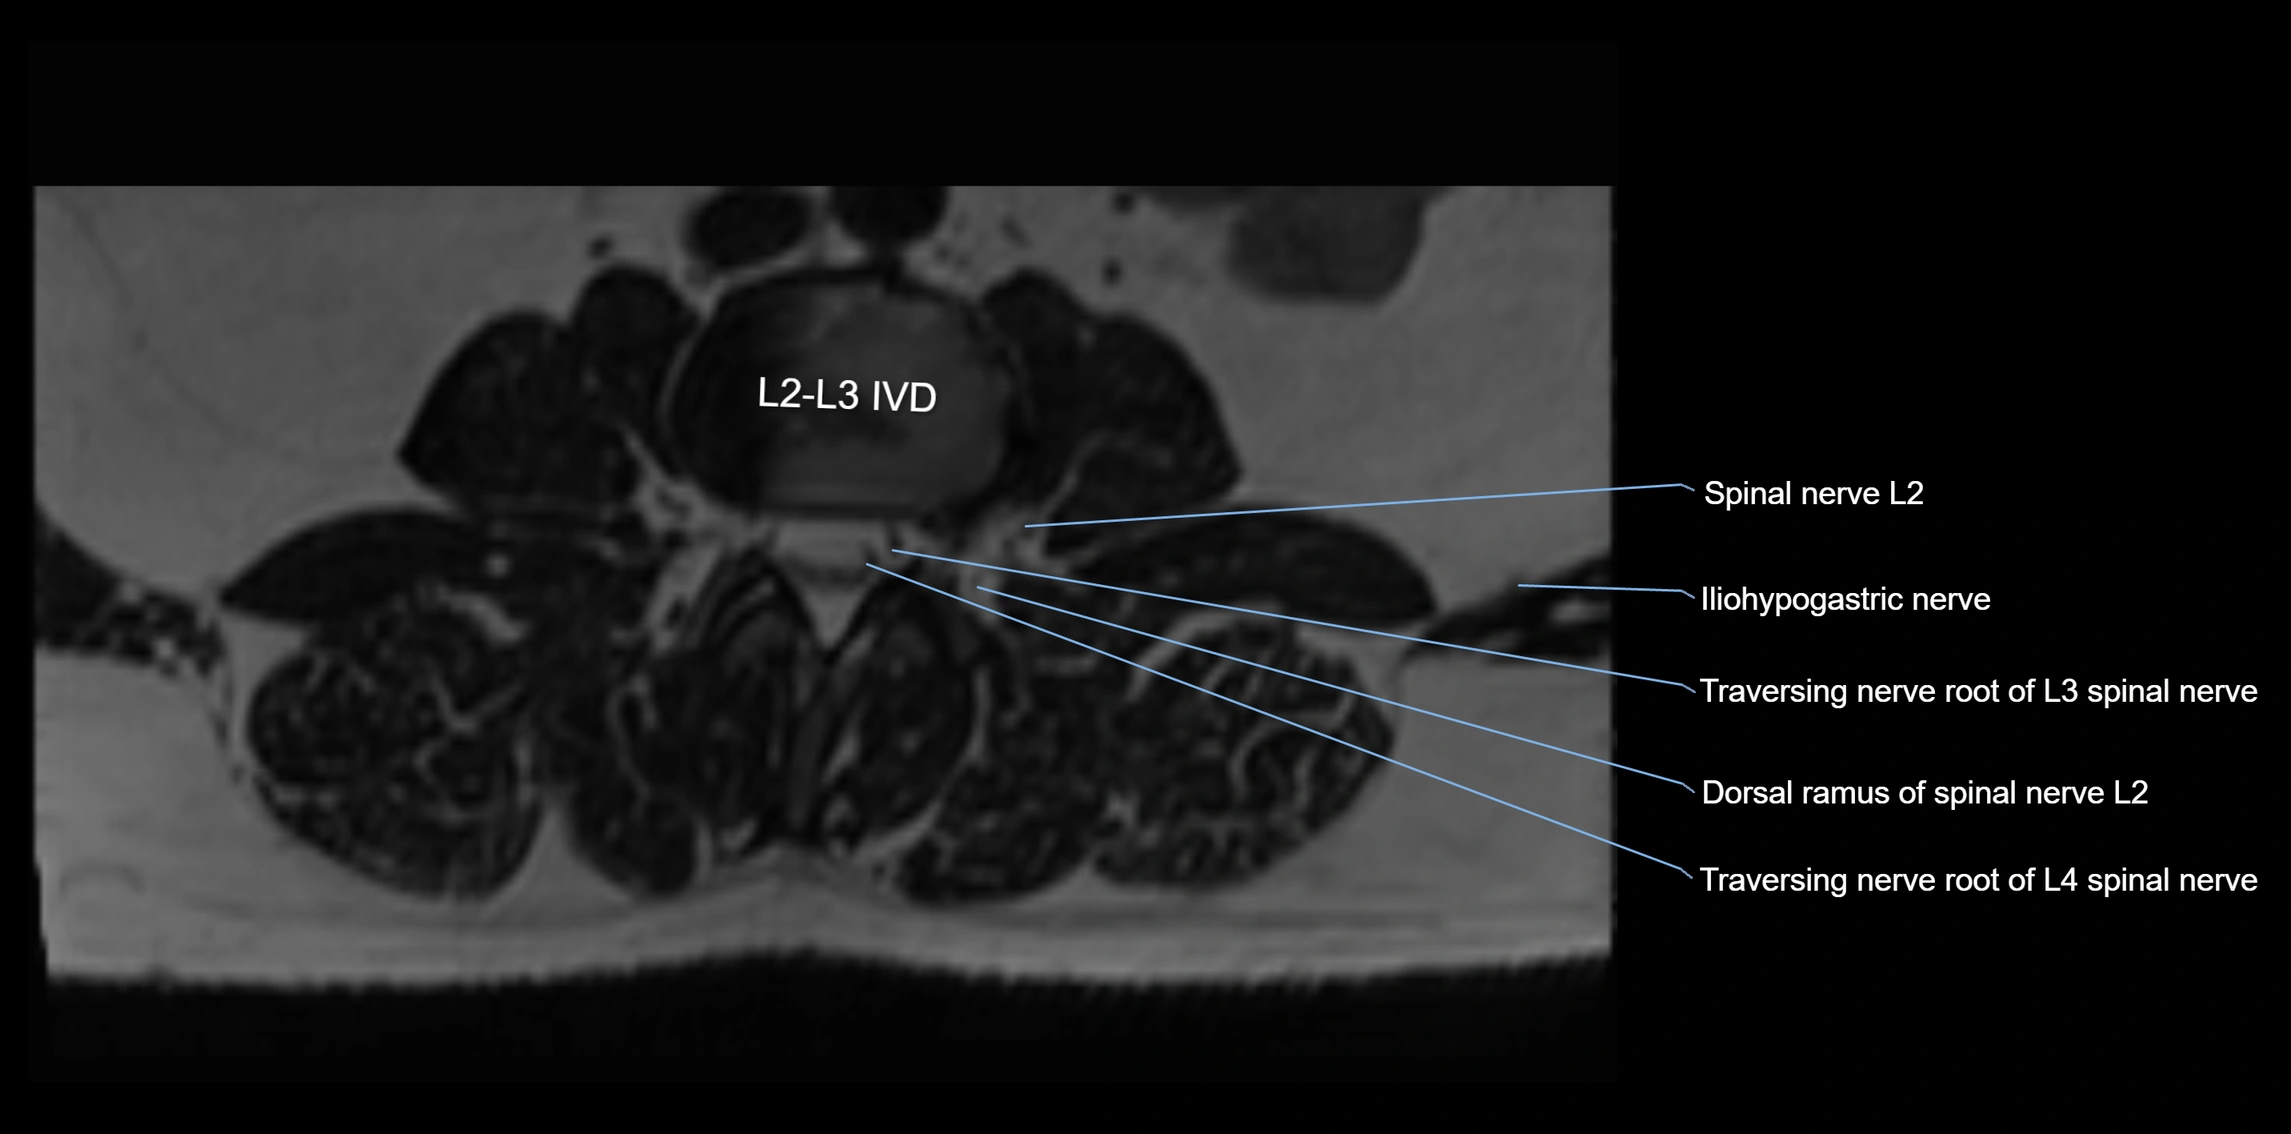

MRI image

image